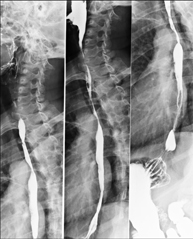

- RX Columna lumbar

Técnica mediante la cual, utilizando rayos X, se obtienen imágenes de la columna lumbar para su estudio. Indicaciones: ciática, traumatismo, dolor lumbar.

- Telerradiología columna

Técnica mediante la cual, utilizando rayos X, se obtienen imágenes de toda la columna vertebral para su estudio, valorando especialmente la presencia de escoliosis y dismetrías pélvicas.